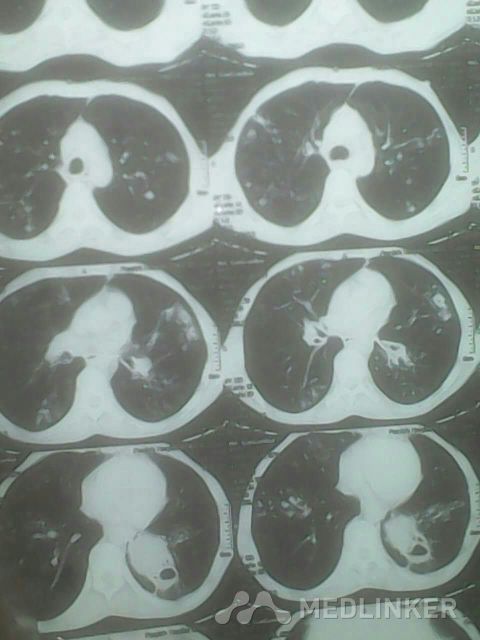

胸部!CT,,考虑什么?

请教各位,下面胸部CT考虑什么?

看这胸部CT?